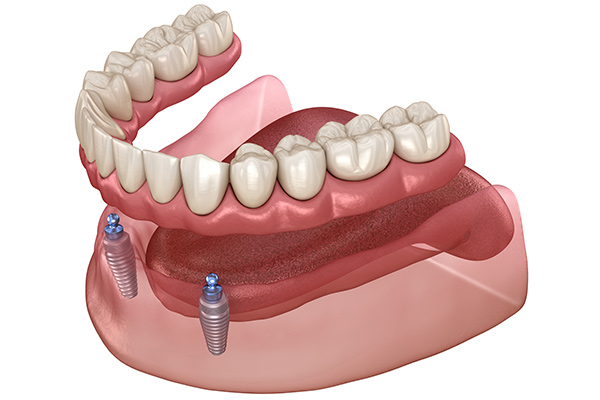

インプラントオーバーデンチャー

総入れ歯の安定性に不満がある患者さんにおすすめなのが、インプラントオーバーデンチャーです。これは、あごの骨に少数のインプラント(通常2~4本)を埋入し、それを入れ歯の土台として利用する方法です。インプラントが入れ歯をしっかりと支えるため、通常の入れ歯よりも格段に安定し、外れにくくなります。全ての歯をインプラントにするよりも費用を抑えつつ、高い安定性を得られる治療法です。